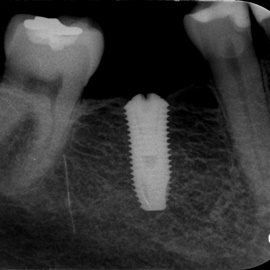

Lat 50, pół roku przed rozpoczęciem leczenia implantologicznego przestał palić papierosy. Znacząca poprawa higieny, pacjent silnie zmotywowany. Po regeneracji kości i rekonstrukcji tkanek miękkich odbudowa sześciu zębów na koronach porcelanowych. Na zdjęciu widoczna ilość i jakość tkanki kostnej po rekonstrukcji. W porównaniu ze stanem początkowym uzyskano znaczącą poprawę warunków kostnych nie do osiągnięcia metodami sterowanej regeneracji kości z użyciem reklamowanych markowych błon kolagenowych i dosypaniem kości z butelki.